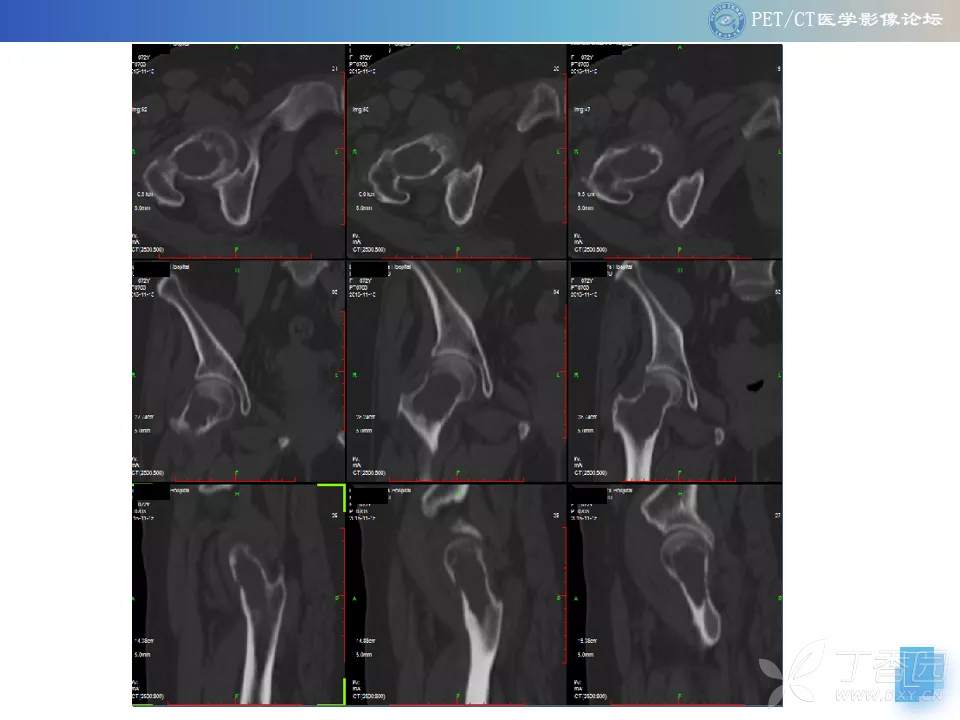

【PET/CT 病例读片】髋关节占位性病变

注:病例来源【PETCT病例读片第二十二期】

查看病例结果及诊断分析请关注公众号【PETCT医学影像论坛】